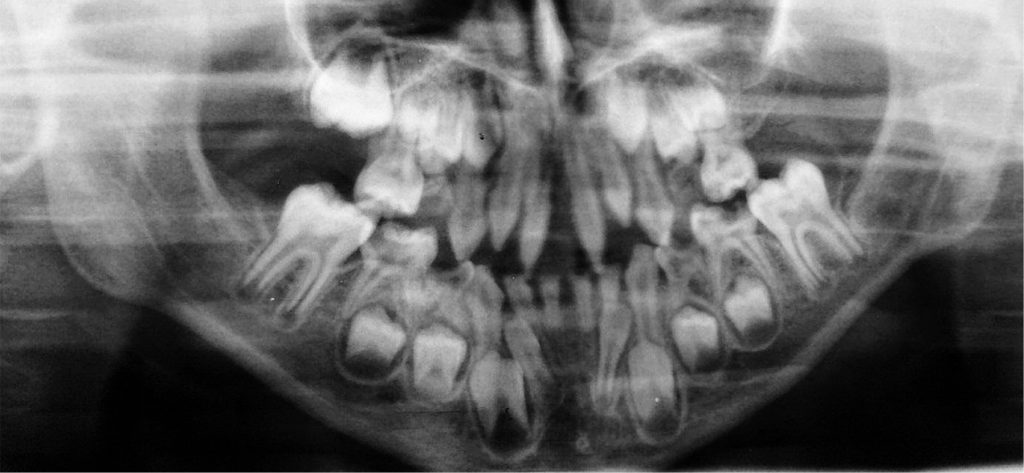

Streszczenie: Częstą wadą współistniejącą z oligodoncją jest występowanie zębów stożkowych, zwanych zębami w kształcie kołka (ang. peg-shaped). Celem pracy było przedstawienie leczenia pedodontycznego – odbudowy kompozytowej zębów stożkowych u siedmioletniego chłopca z hipodoncją. Opisany przypadek wskazuje na istotne znaczenie opieki interdyscyplinarnej oraz ważną rolę pedodonty w planowaniu długoterminowej opieki stomatologicznej nad pacjentem z nieprawidłowościami zębowymi.

Summary: Oligodontia is often accompanied by a common defect: the presence of teeth in the shape of a cone, the so-called peg-shaped teeth.

The aim of the paper is to present a case of paedodontic treatment: a composite reconstruction of peg-shaped teeth in a seven-year-old boy with hypodontia. The described case demonstrates the importance of interdisciplinary care and the essential role of a paediatric dentist in the planning of a long-term dental care of a patient with teeth anomalies.